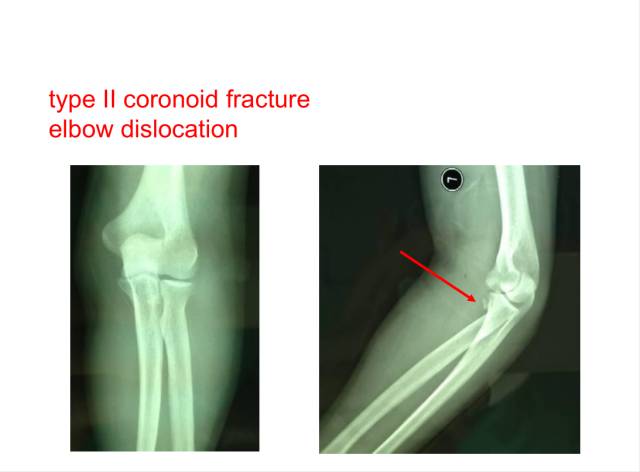

冠突是一个非常重要的稳定结构

• Ⅰ型和Ⅱ型单纯冠状突骨折,发生后方半脱位的风险很小,允许早期活动

• 即使单纯Ⅲ型骨折,在很小的生理应力下也有可能发生后方半脱位,特别是在屈肘60°~105°,支持对Ⅲ型损伤ORIF